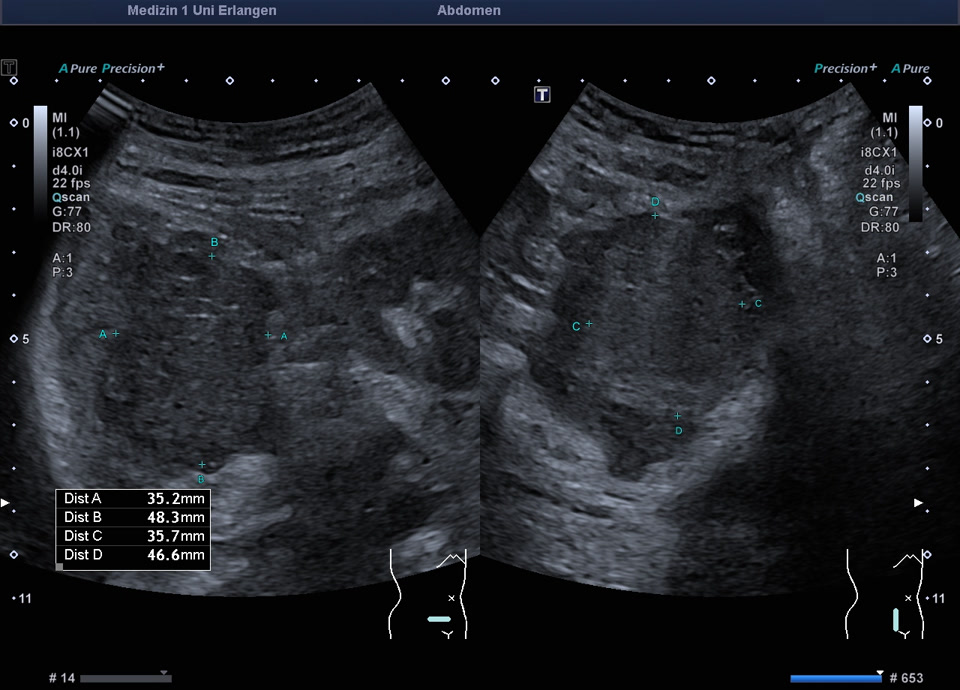

• Subcutaneous metastasis (color Doppler, video)

• Subcutaneous metastasis (color Doppler)

• Psoas metastasis of urothelial carcinoma (color Doppler)